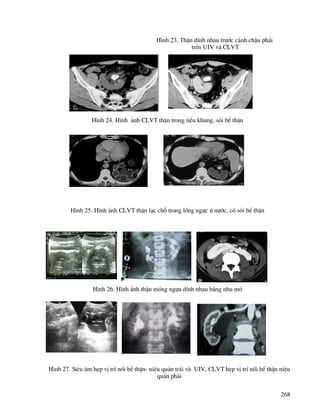

H×nh 11. CLVT u thËn x©m lÊn ®¹i trµng, ®u«i tuþ, thµnh bông

H×nh 12. Chôp phæi th−êng quy vµ CLVT di c¨n phæi cña u thËn